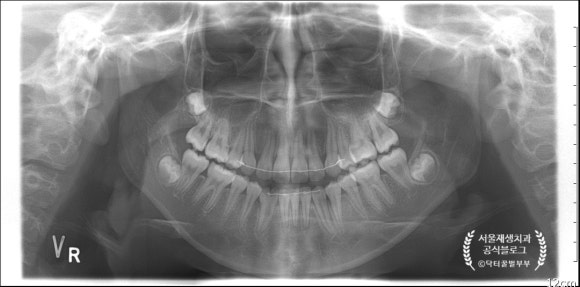

13살 여자어린이인데요,

왼쪽 앞니에 문제가 생겨서 내원했습니다.

인접한 다른 앞니들은 모두 치근 성숙이 완료된 소견인데요,

한 치아만 어째서인지 미성숙 상태 그대로입니다.

경추(=목뼈)와 겹쳐서 파노라마 상에서는 잘 보이지 않는군요.

증명 사진을 한 장 찍어보겠습니다.